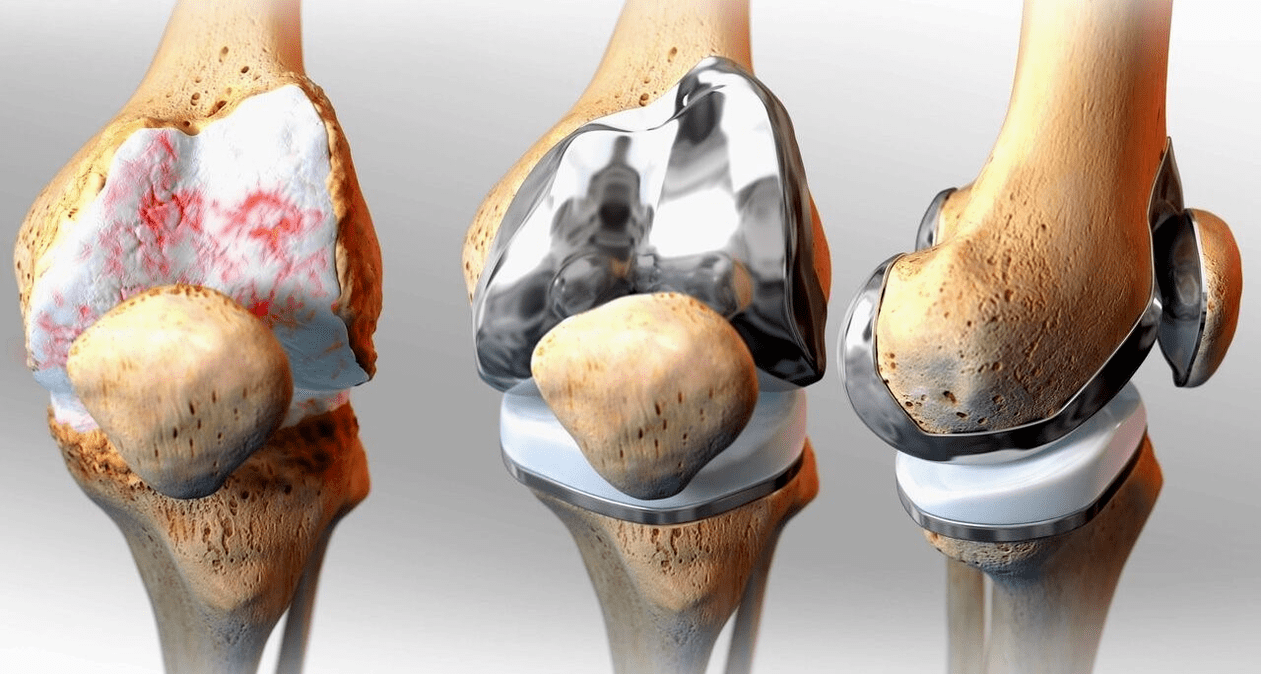

surgery — arthroscopy (method with low trauma for the treatment of intra-articular pathologies and removal of damaged structures), endoprosthetics.

Surgical treatment and endoprosthetics

Endoprosthesis replacement is a common and effective surgical method for the treatment of severe gonarthrosis, which allows you to maintain limb mobility and the ability to lead a full life afterwards.This is a high-tech operation that takes approximately an hour and a half.In the postoperative period, long-term rehabilitation and development of the joint is necessary.After 25-30 years, when the artificial joint wears out, it must be replaced again.